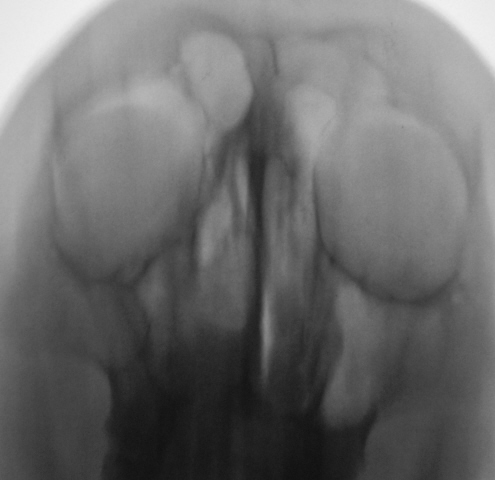

Ваше мнение коллеги по представленным снимкам и томограммам. Каждая иллюстрация представлена в двух вариантах - без обработки изображения и с "обработкой".

Да. Перевернуты только томограммы, на которых левая сторона слева, а правая - справа. В анамнезе была операция, какая, пациент уточнить не может. В настоящее время  появились боли распирающего характера слева, чувство заложенности, направлен на исследование "без диагноза".